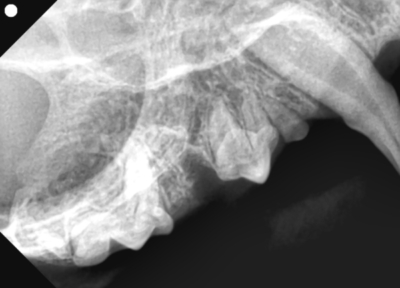

そして歯科レントゲン撮影を行いました。

なにがなにやらわからないと思い、黄色ラインで歯をなぞりました。右上顎です。中央に過剰な歯があり、回転して生えています。

左下顎は正常な数と歯並び

右上顎も同様に中央に回転して生えている過剰歯があります。

左下顎は中央に重なって生えている過剰歯があります。レントゲンで確認しても、乳歯ではなく永久歯と考えられました。これらは過剰歯と呼ばれ、通常より本数が多く歯が生えてきます。かみ合わせが悪くなり、また歯間が狭くなり歯垢がつき、歯周病になりやすいです。そのため、不必要と思われる歯を抜歯しました。また、歯肉の増殖している部分を一部切り取り病理検査用の検体とし、それ以外の部分はメスで切除し正常に近い歯肉の形状に近づけました。